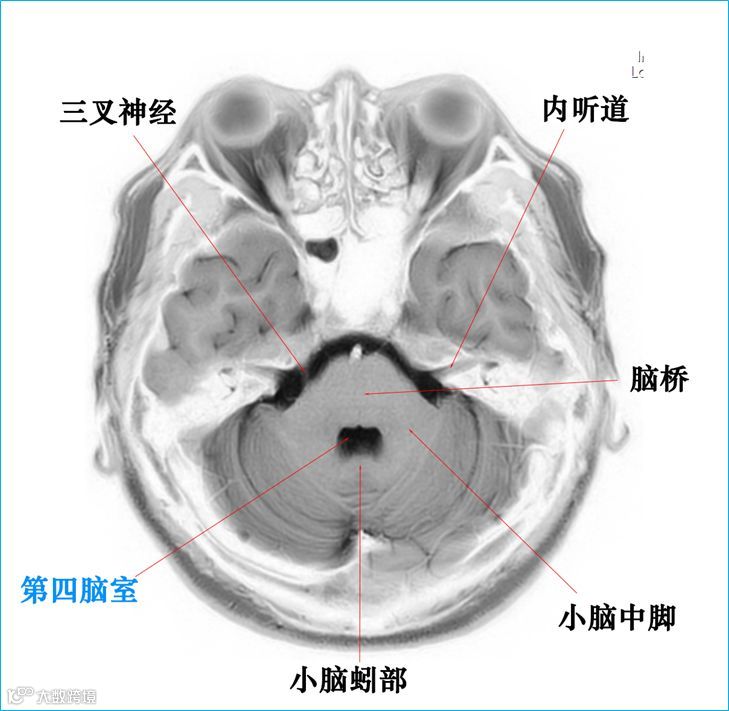

在T2WI反相图学下的颅脑断层解剖(吴晓安老师亲自手动标准)以及标本断层解剖,满满干货,坐在小板凳上,一起学习吧……